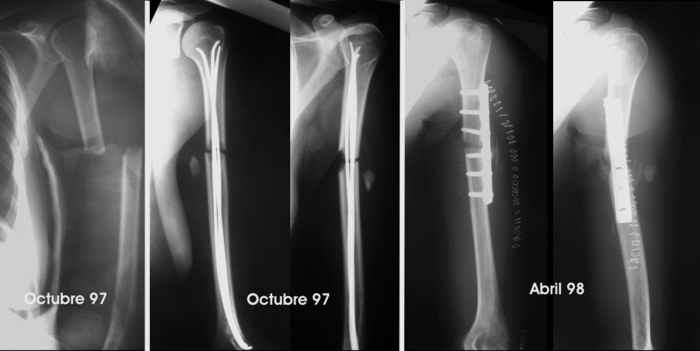

She was close to a tractor power take-off and her clothes caught her. She was pulled towards the tractor and suffered several rib fractures and this humeral fracture (AO-OTA 12-B2). No radial paralysis. She was fixed with Hackettal elastic nailing.

Six months later there was no signs of healing so she accepted to revise the fracture. We used compression plating and autologous iliac bone grafting on April 98.